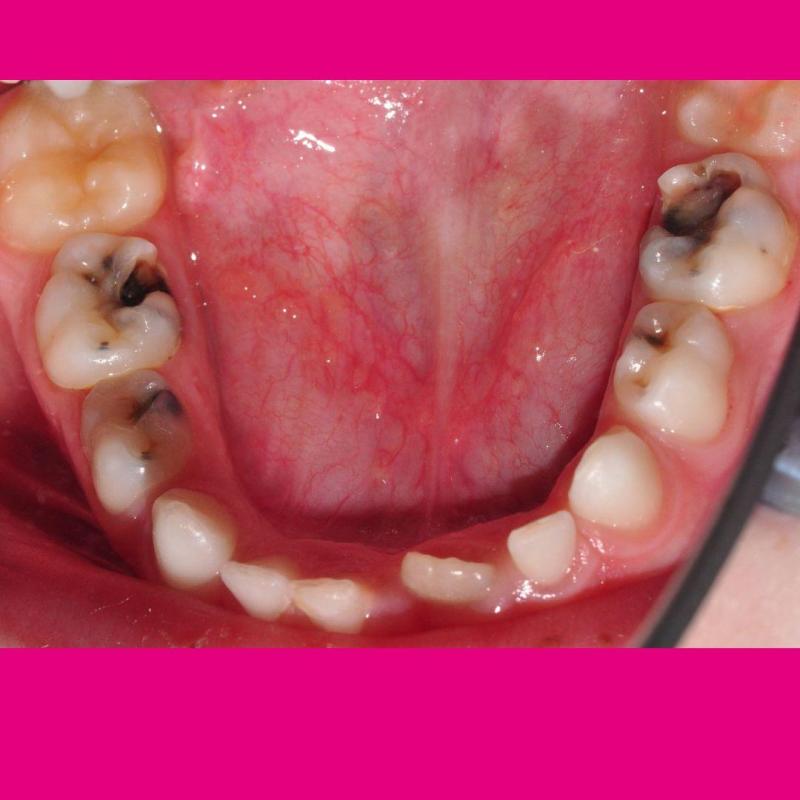

![Kindermund Karies Kindermund Karies]()

19.07.2022

Hilfe, mein Kind hat Karies! Was tun?

Karies an Milchzähnen ist leider sehr verbreitet. Auch wenn die ersten Zähne bald ausfallen, ist eine Behandlung dringend ratsam. Wir erklären, warum. -